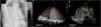

Un varón de 57 años que acudió a urgencias traído por familiares por dificultad respiratoria, malestar general y obnubilación. Llegó a urgencias en situación crítica, por lo que se procedió a la intubación orotraqueal urgente, estabilización y realización de radiografía de tórax (imagen 1). Se objetivó opacidad de la práctica totalidad del pulmón derecho. Se le realizó una ecografía pulmonar para valorar la posible presencia de un derrame pleural, con una sonda sectorial en la línea media axilar (imagen 2). En la misma se objetivó una hepatización pulmonar (letra P) separado del hígado (letra H) por el diafragma (estrella roja). Se descartó la presencia de un derrame pleural. Ante la posibilidad de atelectasia vs. condensación neumónica, se completó el estudio ecográfico (imagen 3), objetivándose vasos mediante un Doppler, adyacentes a la presencia del broncograma aéreo (flecha roja) estableciéndose el diagnóstico de condensación pulmonar. (See Figura 1.)

Imagen 1: Radiografía de tórax. Se objetiva opacidad de la práctica totalidad del pulmón derecho. Imagen 2: Hepatización pulmonar (letra P) separado del hígado (letra H) por el diafragma (estrella roja). Imagen 3: Ecografía doppler de pulmón derecho. Se observa broncograma aéreo (flecha roja).